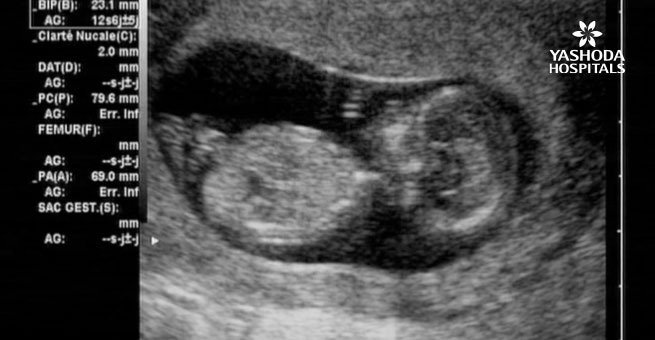

Ultrasound: A fetal sonogram or ultrasound is a safe imaging technique that uses sound waves to produce images of a fetus in the uterus. This test is performed during all stages of pregnancy albeit with different techniques and purposes. It may be of two types:

- Transabdominal ultrasound: A transducer which is a small handheld device is rolled over the abdomen after it is lubricated with jelly and the images are observed on a monitor.

- Transvaginal ultrasound: A wand or probe like transducer is placed in the vagina to transmit images on the screen. It may be recommended if the transabdominal ultrasound doesn’t provide enough information.

A fetal ultrasound in the first trimester helps to:

- Confirm the pregnancy and its location i.e pregnancy outside of the uterus or ectopic pregnancy, or to diagnose any potential miscarriage.

- An early ultrasound examination acts as a key baseline against which later examinations are compared for the evaluation of the growth and development of the fetus. It helps to determine the baby’s gestational age, determine the due date and track milestones throughout pregnancy.

- Confirm the number of fetuses or babies.

- Evaluate the growth and monitor baby’s movement, breathing and heart rate.

- To look for any kind of growth in the fetus that is not normal.

- Determine the risk of certain genetic defects by assessing the fetal nasal bone and Fetal Nuchal Translucency (NT): The nasal bone or the bone of the nose is not visible, or hypoplastic at 11-13 weeks’ pregnancy in fetuses with chromosomal abnormalities and genetic defects like trisomy 21 or Down’s syndrome. Assessment of the nasal bone at 11-13 weeks is used as a screening for trisomy 21 by maternal age.

- Fetal nuchal translucency (NT) and serum biochemistry: An ultrasound in the 12th week is used for the measurement of the thickness of the nuchal translucency. Nuchal translucency is the fluid-filled region at the neck of the fetus. The thickness of more than 2.5 mm may be suggestive of chromosomal abnormalities.